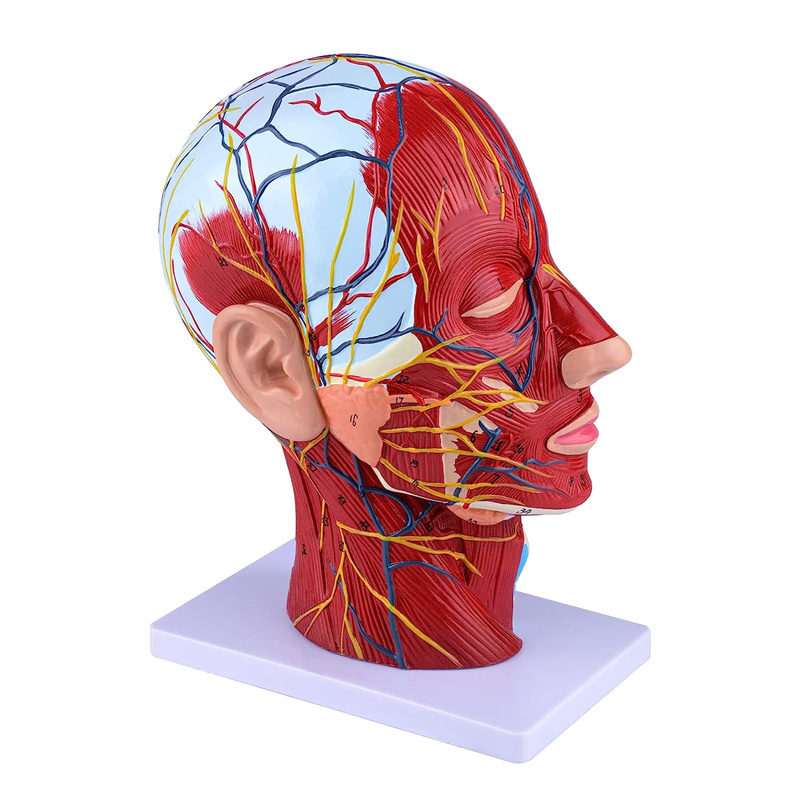

| ਫੀਚਰ | ਮਾਡਲ ਸਿਰ ਅਤੇ ਗਰਦਨ ਦੇ ਅੰਦਰੂਨੀ ਅਤੇ ਬਾਹਰੀ ਪਾਸਿਆਂ ਦੇ ਅੰਦਰੂਨੀ ਰੂਪਨ ਵਿਗਿਆਨ ਦੇ ਨਾਲ-ਨਾਲ ਖੂਨ ਦੀਆਂ ਨਾੜੀਆਂ ਅਤੇ ਨਾੜਾਂ ਦੇ structures ਾਂਚਿਆਂ ਦਾ ਸਥਾਨਕ ਰੂਪ ਵਿਗਿਆਨ ਦਰਸਾਉਂਦਾ ਹੈ, ਅਤੇ ਇੱਥੇ 84 ਹਿੱਸੇ ਹਨ ਜੋ ਕੁੱਲ ਵਿੱਚ ਸੰਕੇਤ ਦਰਸਾਉਂਦੇ ਹਨ. |

【ਸਤਹੀ ਨਿ ur ਰੋਵਸਕੂਲਰ ਮਾਸਪੇਸ਼ੀ ਦਾ ਮਾਡਲ】 ਉੱਚਿਤ ਵਿਸਥਾਰਪੂਰਕ, ਨੰਬਰ ਮਾਰਕ ਕੀਤੇ, ਕੰਬਦੇ ਕੰ the ੇ, ਨਾੜੀ ਅਤੇ ਗਰਦਨ ਦੇ ਅੰਦਰੂਨੀ structures ਾਂਚਿਆਂ ਦੀ ਸਮਝ ਨੂੰ ਡੂੰਘਾ ਕਰੋ. ਲਾਲ-ਧਮਣੀ, ਨੀਲੀ-ਨਾੜੀ, ਪੀਲੇ-ਨਸ.

【ਵਿਸ਼ੇਸ਼ਤਾਵਾਂ】 ਦਾ ਸਾਹਮਣਾ ਕੀਤੇ ਚਿਹਰੇ ਦੀਆਂ ਸਤਹੀ ਮਾਸਪੇਸ਼ੀਆਂ ਨੂੰ ਦਰਸਾਉਂਦਾ ਹੈ; ਸਤਹੀ ਖੂਨ ਦੀਆਂ ਨਾੜੀਆਂ ਅਤੇ ਚਿਹਰੇ ਦੀਆਂ ਨਾੜੀਆਂ ਅਤੇ ਖੋਪੜੀ; ਪੈਟੀਡ ਗਲੈਂਡ ਅਤੇ ਵੱਡੇ ਸਾਹ ਦੀ ਨਾਲੀ ਦੇ ਅੰਦਰੂਨੀ structures ਾਂਚਿਆਂ; ਸਰਵਾਈਕਲ ਰੀੜ੍ਹ ਦੀ ਸੋਗਿਤਲ ਕਰਾਸ-ਸੈਕਸ਼ਨ structure ਾਂਚਾ.

ਇਹ ਮਾਡਲ ਮਨੁੱਖ ਦੇ ਸੱਜੇ ਸਿਰ ਅਤੇ ਮਨੁੱਖ ਦੇ ਮੱਧ ਸੇਂਟਟਲ ਭਾਗ ਦਾ ਵੇਰਵਾ ਦਰਸਾਉਂਦਾ ਹੈ. ਸਤਹੀ ਵੀ ਸ਼ਾਮਲ ਹੈ

ਖੁੱਲੇ ਚਿਹਰੇ ਦੇ ਮਾਸਪੇਸ਼ੀ; ਸਤਹੀ ਖੂਨ ਦੀਆਂ ਨਾੜੀਆਂ ਅਤੇ ਚਿਹਰੇ ਅਤੇ ਖੋਪੜੀ ਦੀਆਂ ਨਾੜੀਆਂ; ਅੰਦਰੂਨੀ structures ਾਂਚਿਆਂ

ਪੈਟੀਡ ਗਲੈਂਡ ਅਤੇ ਉਪਰਲੇ ਸਾਹ ਦੀ ਨਾਲੀ; ਸਰਵਾਈਕਲ ਰੀੜ੍ਹ ਦੀ ਸੋਗਿਤਲ ਕਰਾਸ-ਸੈਕਸ਼ਨ structure ਾਂਚਾ.

ਮਾਡਲ ਨੇ ਸਿਰ ਅਤੇ ਗਰਦਨ ਅਤੇ ਗਰਦਨ ਦੇ ਮੱਧਮ ਅਤੇ ਪਾਰਦਰਸ਼ੀ ਸਮੂਹਾਂ ਅਤੇ ਇਸ ਦੇ ਨਾੜੀ ਅਤੇ ਨਸਾਂ ਦੇ structures ਾਂਚਿਆਂ ਅਤੇ ਨਸਾਂ ਦੇ structures ਾਂਚਿਆਂ ਦਾ ਸਥਾਨਕ ਰੂਪ ਵਿਗਿਆਨ ਅਤੇ ਇਸ ਦੇ ਨਾੜੀ ਅਤੇ ਨਸਾਂ ਦੇ structures ਾਂਚਿਆਂ ਦਾ) ਕੁੱਲ 100 ਸਾਈਟ ਸੂਚਕਾਂ ਦੇ ਨਾਲ ਦਿਖਾਇਆ ਗਿਆ ਹੈ.

ਇਹ ਮਾਡਲ ਇੱਕ ਕੁਦਰਤੀ ਵੱਡਾ ਸਿਰ ਅਤੇ ਗਰਦਨ ਸਤਹੀ ਨਿ ur ਰੋਵਸਕੁਲਰ ਮਾਸਪੇਸ਼ੀ ਮਾਡਲ, 1 ਕੰਪੋਨੈਂਟ, ਚਿਹਰੇ ਅਤੇ ਖੋਪੜੀਆਂ ਦੇ ਸਤਹੀ ਮਾਸਪੇਸ਼ੀਆਂ ਦੇ ਵੇਰਵੇ ਦਿਖਾਉਂਦੇ ਹੋਏ, ਨਸਾਂ ਅਤੇ ਪੈਰੋਟਿਡ ਗਲੈਂਡ ਅਤੇ ਵੱਡੇ ਸਾਹ ਦੀ ਨਾਲੀ ਦਾ ਮੈਡੀਅਲ ਬਣਤਰ, ਅਤੇ ਸਰਵਾਈਕਲ ਰੀੜ੍ਹ ਦੀ ਸੋਗਟਲ ਸੈਕਸ਼ਨ ਦਾ structure ਾਂਚਾ